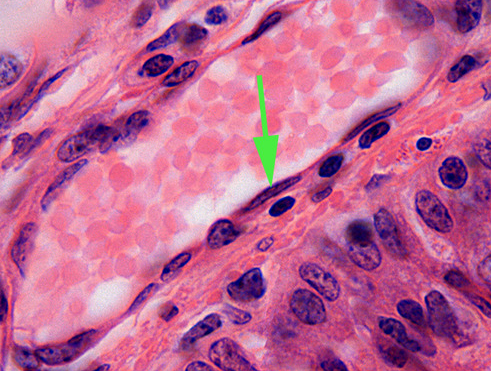

What is the name of the layer indicated by the green arrow? endothelium

The black twisted line is elastic tissue found in elastic arteries. The squiggly line is called the internal elastic membrane.

What is the name of the layer indicated by the green arrow? tunica externa